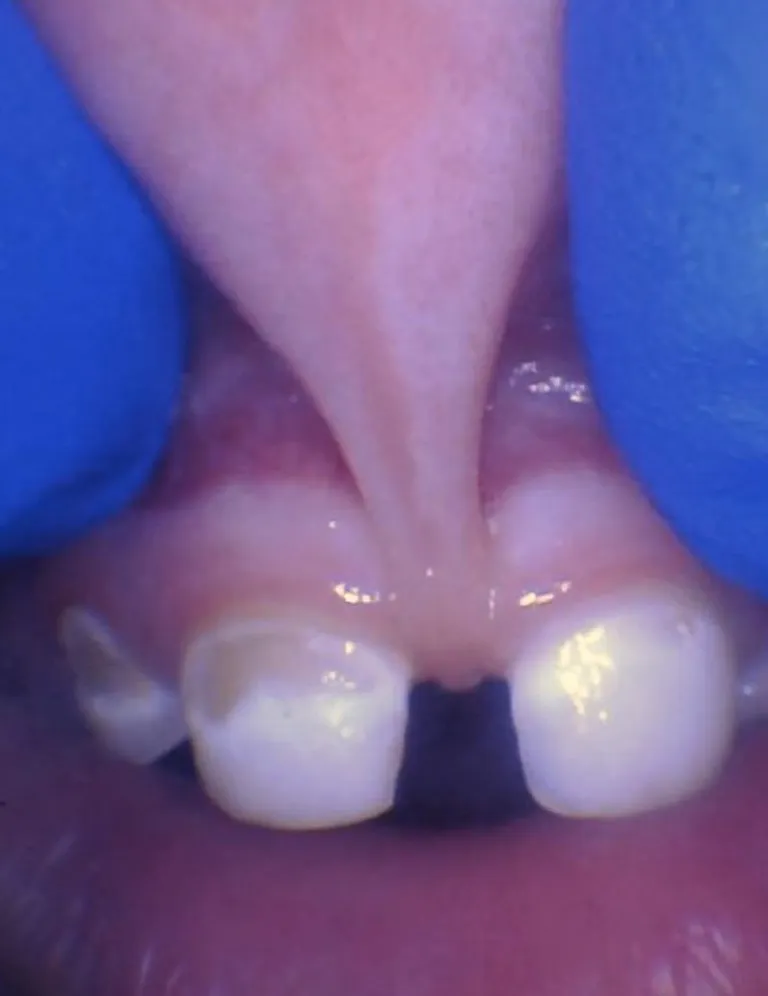

Bébé - Spectre de restrictions d'un FR labial

Enfant - Spectre de restrictions d'un FR labial